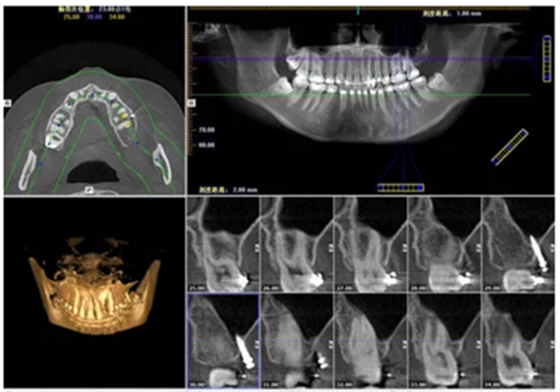

【數(shù)字化影像獲得準(zhǔn)確信息】

目前CBCT 廣泛應(yīng)用在口腔種植術(shù)前診斷與設(shè)計(jì)、口腔頜面部骨折和腫瘤、牙周疾病、顳下頜關(guān)節(jié)疾病、牙體牙髓疾病等領(lǐng)域,很大程度上取代了傳統(tǒng)的放射線檢查技術(shù)。CBCT 將掃描的頜骨影像數(shù)據(jù)導(dǎo)入相應(yīng)軟件中進(jìn)行三維重建,并進(jìn)行準(zhǔn)確測(cè)量,從而可以全方位的進(jìn)行手術(shù)模擬,進(jìn)而合理設(shè)計(jì)種植體的型號(hào)尺寸,同時(shí)可以觀測(cè)種植體與上頜竇及下牙槽神經(jīng)管之間的距離,并且可以對(duì)頜骨骨量骨質(zhì)進(jìn)行評(píng)估,以及模擬未來修復(fù)體與鄰牙對(duì)頜牙的位置關(guān)系等。